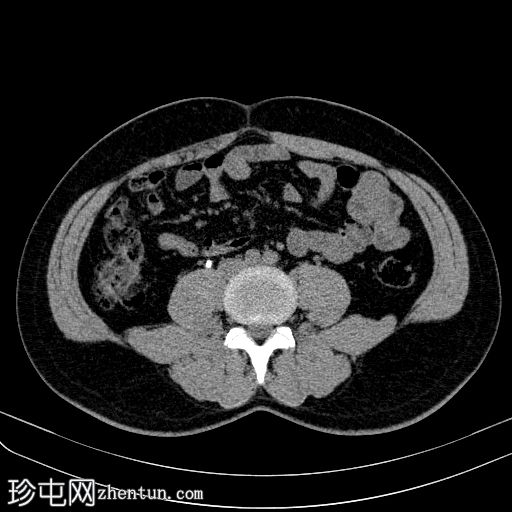

右侧输尿管支架置入。随访CT扫描。

CT

轴位

平扫

右侧输尿管双J管置入良好,自右肾盂延伸至膀胱。

未见肾积水或肾周积液。

未见输尿管周围脂肪条索状改变。

输尿管支架常用于缓解各种原因引起的尿路梗阻。置入可采用顺行或逆行途径。